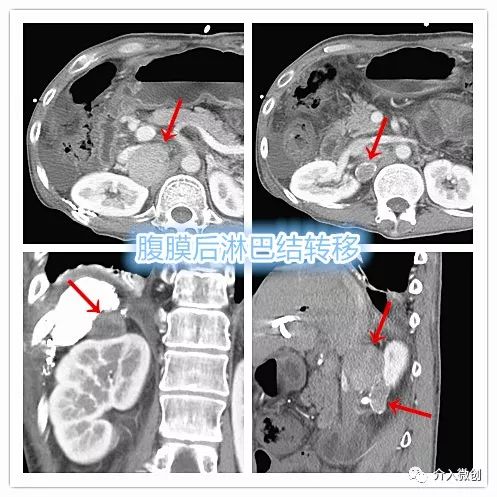

中年男性肝癌患者,经综合介入治疗后肝内病灶控制稳定,近期复查AFP明显升高,CT检查提示腹膜后多发肿大淋巴结,考虑肿瘤进展转移。

肝癌并腹膜后淋巴结转移